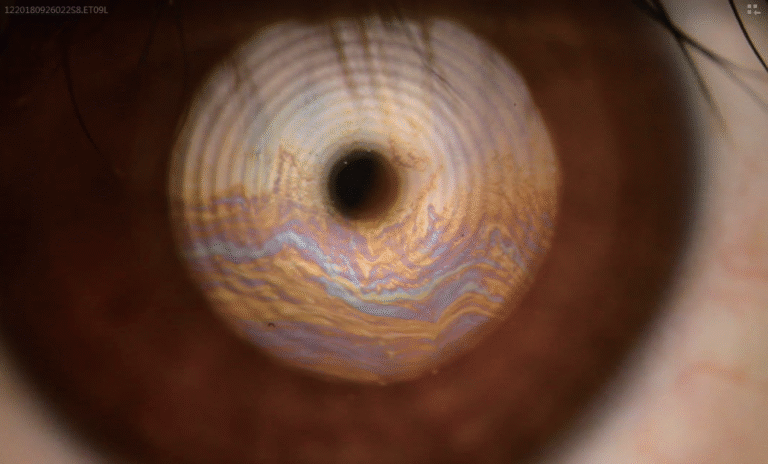

Precision Optics

Premium Optical System

High-resolution visualization across a wide range of magnifications. Multi-coated optics deliver distortion-free anterior segment imaging for confident clinical assessment.

- 5 Step Magnification: 6×, 10×, 16×, 25×, 40×

- 24 Megapixel SLR Camera

- Automatic Digital Optimization

- Automatic Eye Position Recognition for Digital Acquisition